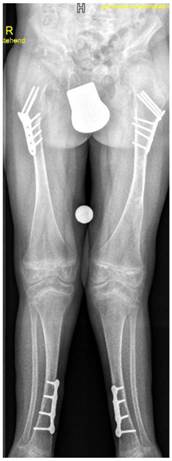

A-9-year-old boy with Stickler syndrome type I manifested premature osteoarthritis matching grade II of Kellgren-Lawrence grading scale with marked narrowing of the joint spaces associated with osteoporosis and coxa valga. Note the flattening of the capital femoral epiphysis, valgus deformity of the tibia, severe valgus of the ankle joint and calcaneovalgus deformity of both feet. Gradual deformity correction by temporary hemiepiphysiodeses of the proximal and distal medial epiphyses using 8 plates was performed to realign the lower limbs and to enable the child to walk and to lessen pain (fig 11)

Fig 11

A-9-year-old boy with Stickler syndrome type I manifested premature osteoarthritis matching grade II of Kellgren-Lawrence grading scale with marked narrowing of the joint spaces associated with marked osteoporosis and coxa valga. Note the flattening of the capital femoral epiphysis, valgus deformity of the tibia, severe valgus of the ankle joint and calcaneovalgus deformity of both feet. Gradual deformity correction by temporary hemiepiphysiodeses of the proximal and distal medial epiphyses using 8 plates was performed to realign the lower limbs and to enable the child to walk and to lessen pain.